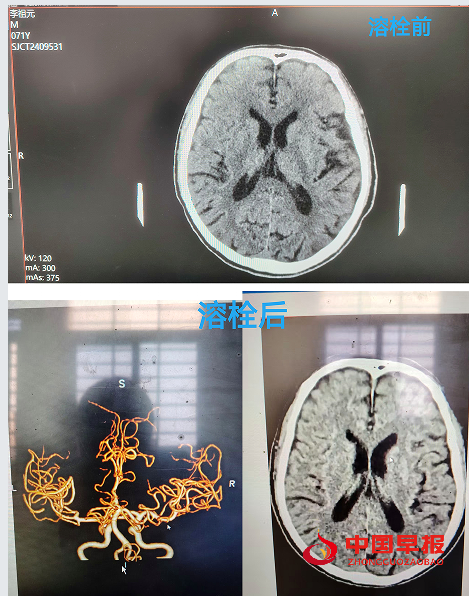

湖北荆门沙洋县沈集镇中心卫生院:成功完成首例急性脑卒中溶栓 开启救治新篇章

中国早报湖北沙洋讯(记者 王光兴 通讯员 构月华 毛草婷)3月6日,湖北荆门市沙洋县沈集镇中心卫生院成功完成首例急性脑卒中溶栓治疗,这是该院在医疗技术领域的重大突破,也为区域内患者带来了新希望。

当天下午13时许,沈集镇雨林村的李爷爷在家中突发口角歪斜、言语含糊、左侧肢体无力,家属发现后,迅速将其送至沈集镇中心卫生院急诊室内,争分夺秒的战斗悄然打响,医护人员迅速启动“脑卒中绿色通道”。经过一系列检查,确诊患者为急性脑卒中且处于溶栓时间窗内,时间就是生命,医护人员立即对患者实施静脉溶栓治疗,治疗过程中,医护人员紧密配合,紧盯老人各项生命体征的细微变化,确保每一个环节都精准无误。溶栓后,患者生命体征稳定。为进一步巩固治疗效果,老人被转送至上级医院进行后续治疗,1小时后,经上级专家反馈患者状态明显好转,溶栓效果良好。

这次急性脑卒中溶栓治疗的成功,也是该院卒中防治站建设达标的强有力证明。未来,沈集镇中心卫生院将始终秉承“以患者为中心”的服务理念,不断提升医疗技术水平和服务质量,为广大群众的生命健康保驾护航,在守护健康的道路上,永不止步,再创佳绩。